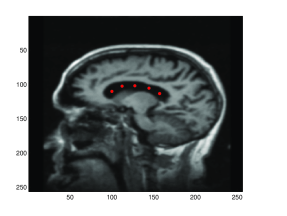

In this paper, we use higher-order momentum distributions in the LDDMM registration framework to obtain a deformation parametrization that increases the capacity of sparse approaches with a basis consisting of interpretable elements. We show how the higher-order representation model locally affine transformations, and we use the compact deformation description to register points and images using very few parameters. We illustrate how the deformation coded by the higher-order momenta can be directly interpreted and that it represents information directly useful in applications: with low numbers of control points, we can detect the expanding ventricles of the patient shown in Figure 1.

Refer to caption

(a) Baseline with control points.

Fig. 1: Progressing Alzheimer’s disease cause atrophy and expansion of the ventricles. By placing five deformation atoms in the ventricle area of the baseline MRI scan [20] and by using higher-order momenta, we can detect the expansion. (a) The position of the deformation atoms shown in the baseline scan; (b) the follow up scan; (c) the log\log-Jacobian determinant of the generated deformation in the ventricle area (red box in (b)); (d) the vector field at t=0𝑡0t=0 of the generated deformation. The logarithm of the Jacobian determinant and the divergence at the deformation atoms are positive which is in line with the expected ventricle expansion, confer also Figure 7.